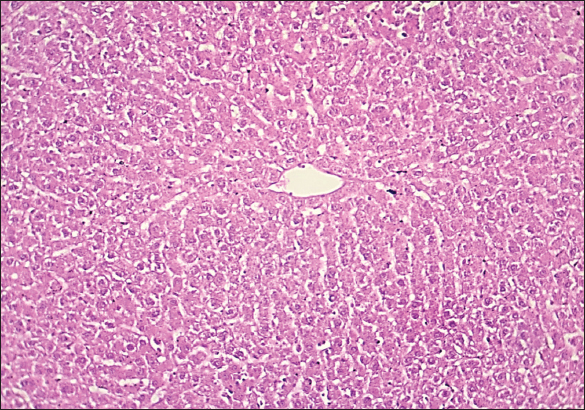

Fig. 2. Histological section of liver in rats drenched with 0.6 mg/kg citalopram and treated with 10 mg/kg J. regia pulp extract. The section shows the normal histological structure of hepatic tissue without any significant occupied lesion (H and E stain 100X).